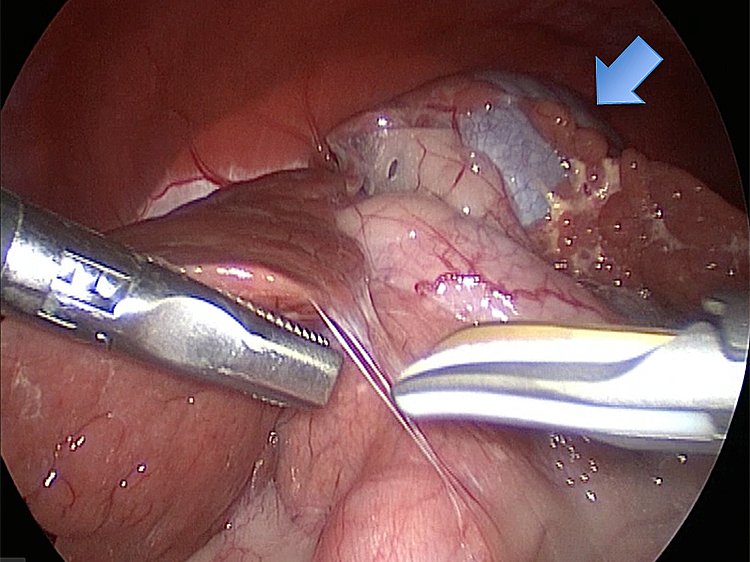

他院より紹介。胆嚢炎がひどく繰り返す嘔吐がありました。 腹膜と一部横隔膜に胆嚢ががっちりと癒着していました。 体重が2kgと体も小さかったのですが、飼い主さんの希望もあり、腹腔鏡下で手術を実施することになりました。

丁寧に丁寧に出血をコントロールしながら少しずつ手術をすすめていきます。

癒着(矢印)がひどく胆嚢を確認することができませんでした。 このように癒着しているときはギリギリで剥がすとひどく出血をおこすことがあるので無理にはがそうとしないで、脂肪の血管に注意しながら脂肪ごと剥がしていきます。